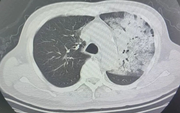

• Nam sinh trung học sốt 5 ngày rồi tử vong, bác sĩ cảnh báo: Bệnh phổ biến nhưng không thể xem nhẹ

Nam sinh trung học sốt 5 ngày rồi tử vong, bác sĩ cảnh báo: Bệnh phổ biến nhưng không thể xem nhẹ

Nam sinh xuất hiện sốt và nhiều biểu hiện khó chịu nhưng trì hoãn điều trị suốt 5 ngày. Khi được gia đình đưa vào khoa cấp cứu, em đã trong tình trạng kiệt sức toàn thân. Kết quả kiểm tra khiến bác sĩ không khỏi bàng hoàng.